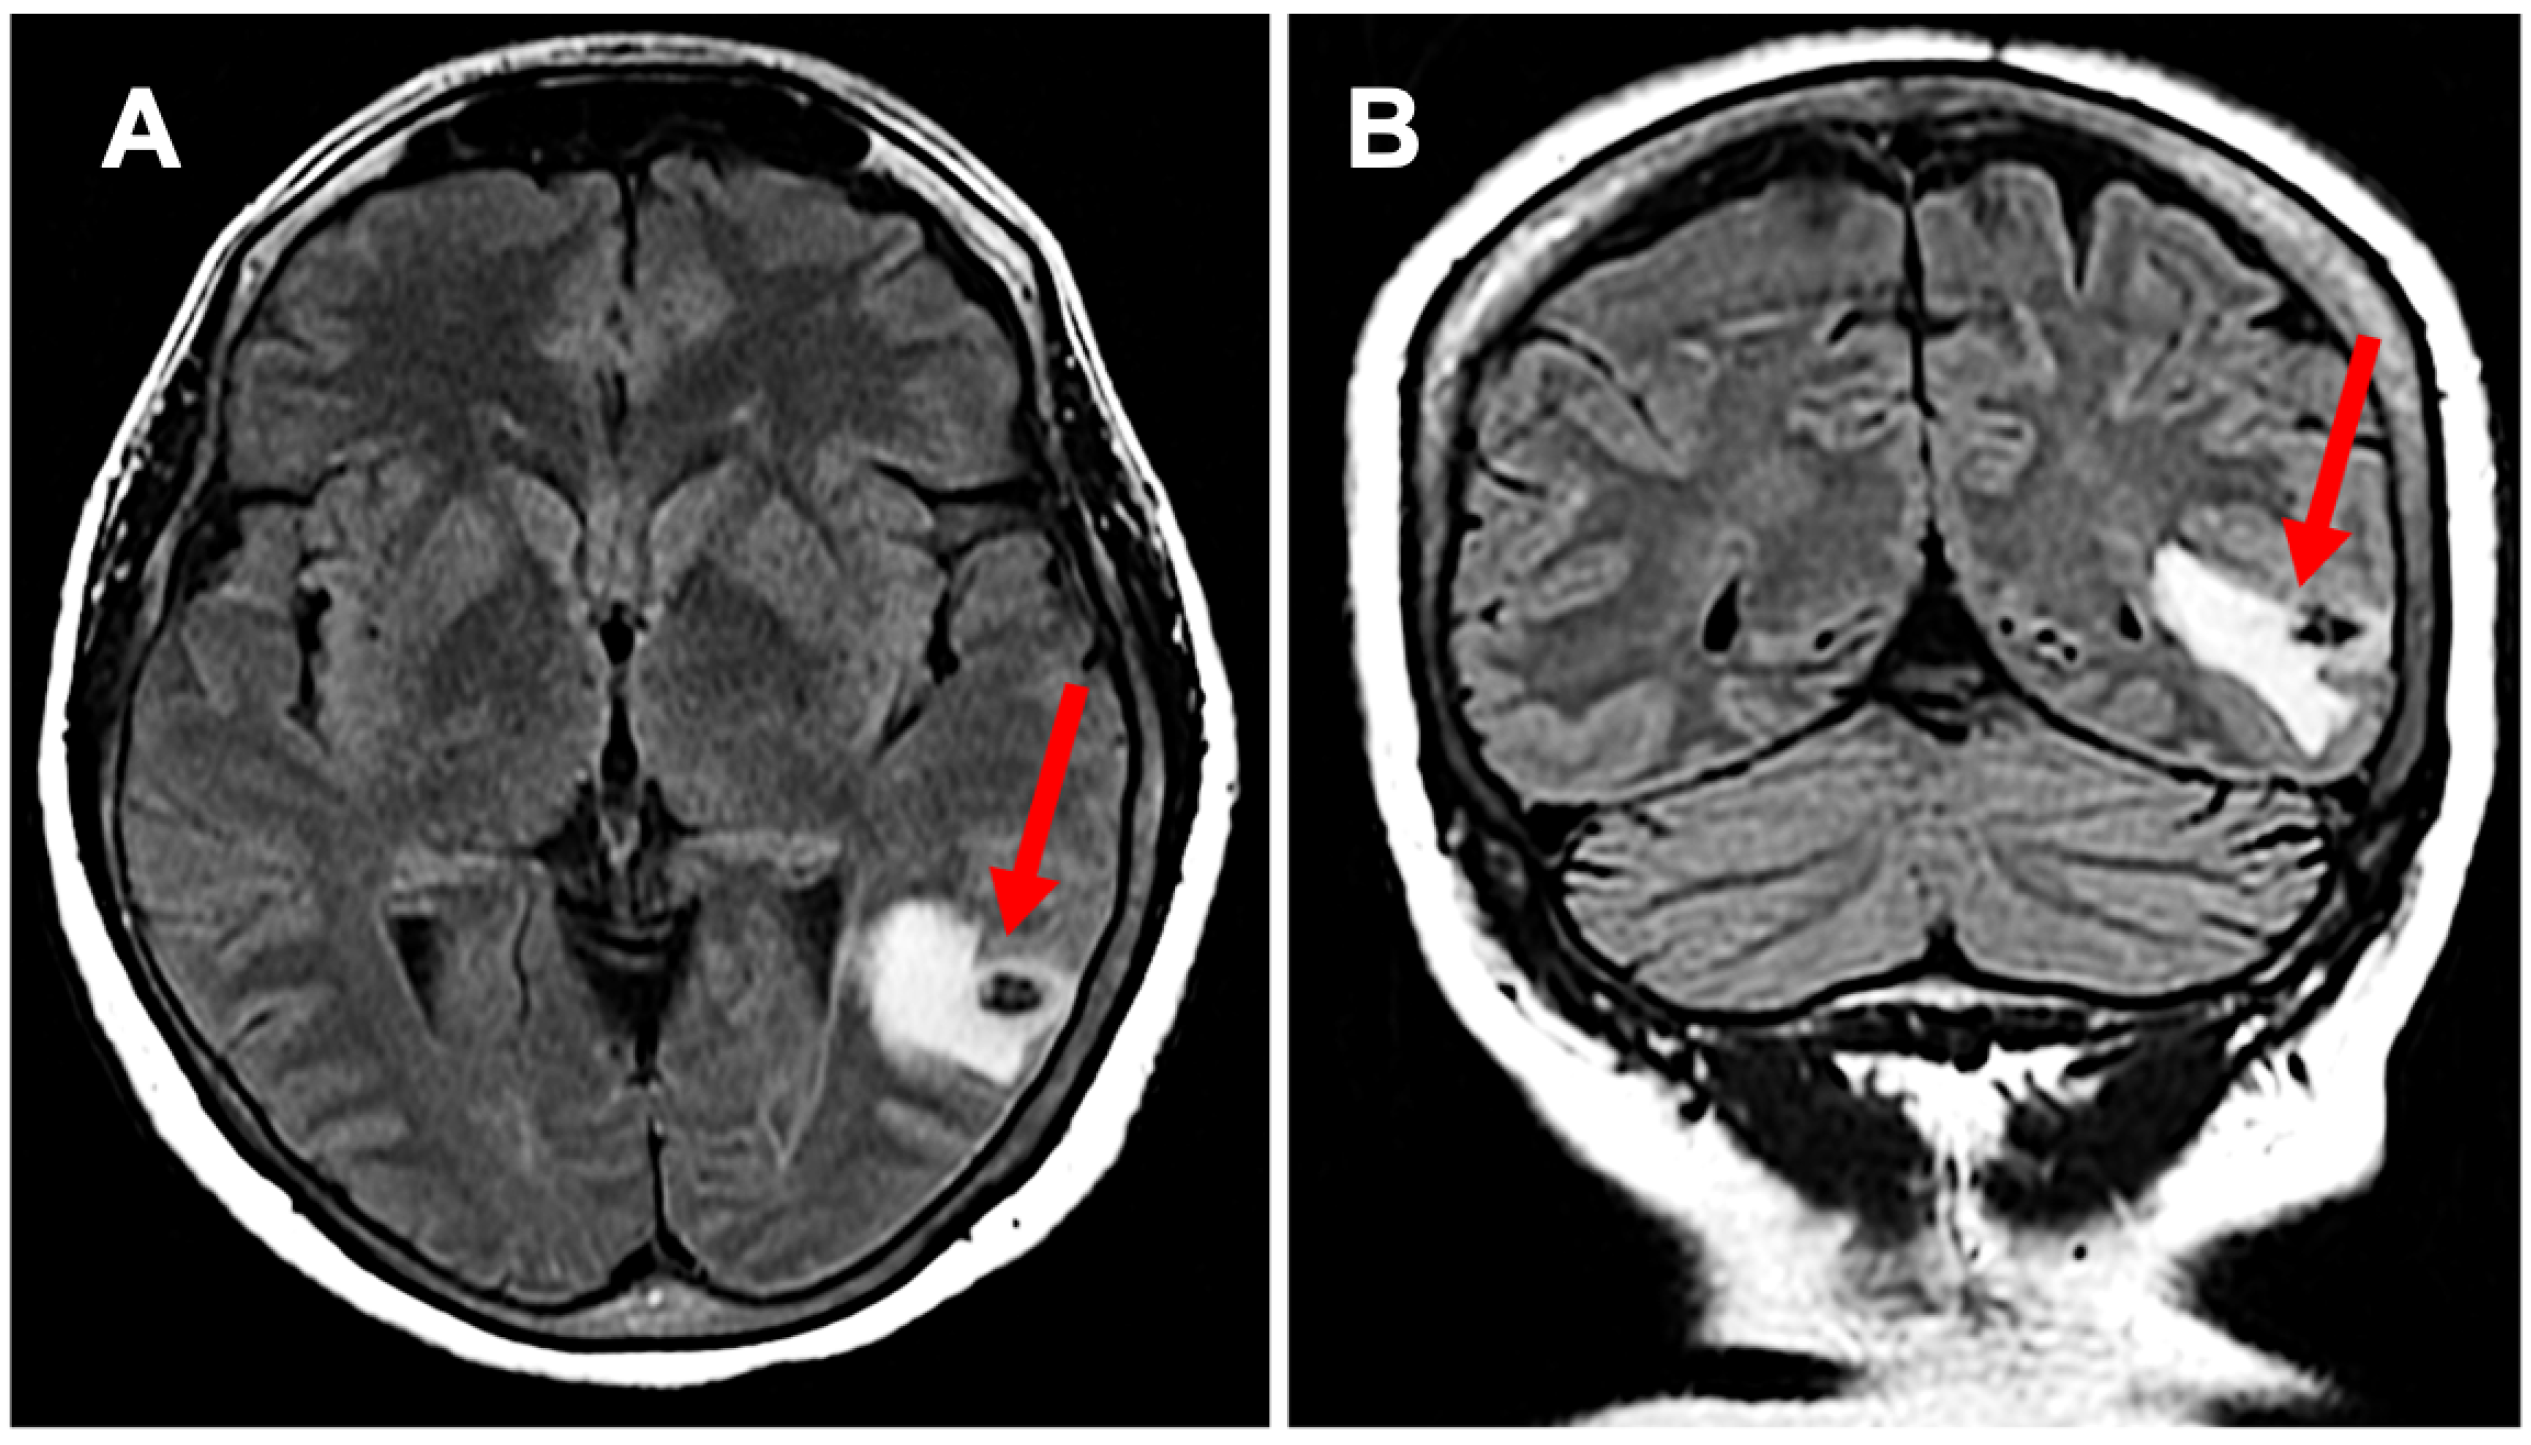

A 64-year-old Hispanic female presented with persistent anomic aphasia for several weeks, accompanied by intermittent occipital headaches and paresthesia in the left upper and lower extremities. She denied any motor deficits or other systemic symptoms. On examination, her vital signs were within normal limits except for elevated blood pressure (181/85 mmHg). Her past medical history was significant for NCC and obesity, diagnosed in 1996 after experiencing seizures following travel to the Dominican Republic, where she had consumed undercooked meat. Brain imaging at that time confirmed NCC, and she was treated with a single course of albendazole in 1998. Her seizures were well controlled with phenytoin and carbamazepine, later transitioning to levetiracetam for improved management. She had also undergone bariatric surgery in 2016 and had been receiving semaglutide for weight reduction therapy over the past six months. The initial laboratory workup, including inflammatory markers (Table 1), was largely unremarkable except for a positive enzyme-linked immunosorbent assay (ELISA) for TS. Brain imaging performed in 2024 revealed NCC reactivation, characterized by localized inflammation and cystic changes following semaglutide therapy [Figure 1]. Notably, prior brain imaging from 2021, before semaglutide initiation, had shown no evidence of active NCC [Figure 2].

Figure 1. Subpanel (A) highlights neurocysticercosis surrounded by edema in a transverse view (red arrow), while subpanel (B) demonstrates the expansion of edema in a coronal view (red arrow); this activation developed while the patient was on semaglutide.